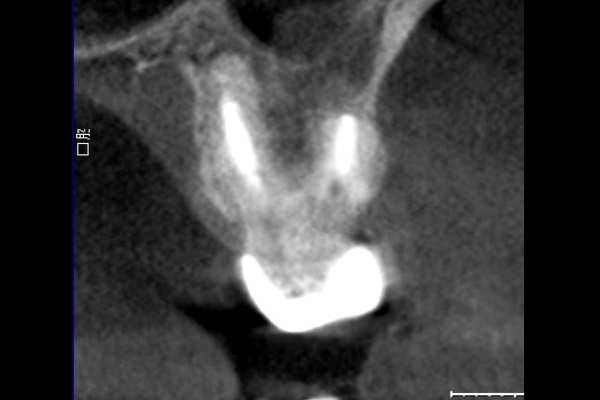

【札幌駅前】精密根管治療

20代女性の大臼歯(奥歯)の症例

- 主訴

- 「時々歯茎が腫れる」とのことでご来院されました。数週間前から症状があり、他の医院では「抜歯の可能性がある」と言われ、不安に感じていらっしゃいました。

- 期間

- 治療期間2ヶ月、治療回数3回、レントゲン写真で治癒を確認できるまでの期間6ヶ月

- ●精密根管治療(大臼歯)154,000円(税込)

- 治療内容

- 1.古い被せ物の除去と虫歯の徹底除去

まず、古い銀歯を外し、内部に広がっていた虫歯を丁寧に取り除きました。

2.マイクロスコープ下での根管治療

唾液などによる細菌の侵入を防ぐ「ラバーダム」を装着し、マイクロスコープ(歯科用顕微鏡)で根管内を数十倍に拡大しながら治療を進めました。複雑な形状の根管の内部まで、汚染された組織を徹底的に洗浄・消毒します。

3.根管充填(こんかんじゅうてん)

根管内が完全にクリーンになったことを確認し、再感染を防ぐために専用の薬剤で隙間なく密閉しました。

4. 土台と被せ物の作製

歯の強度を補うための土台を立て、最終的なセラミックの被せ物を作製し、装着しました。

- 治療に伴うリスク

- 少しでも汚染物質が残ると再発のリスクが高まります。